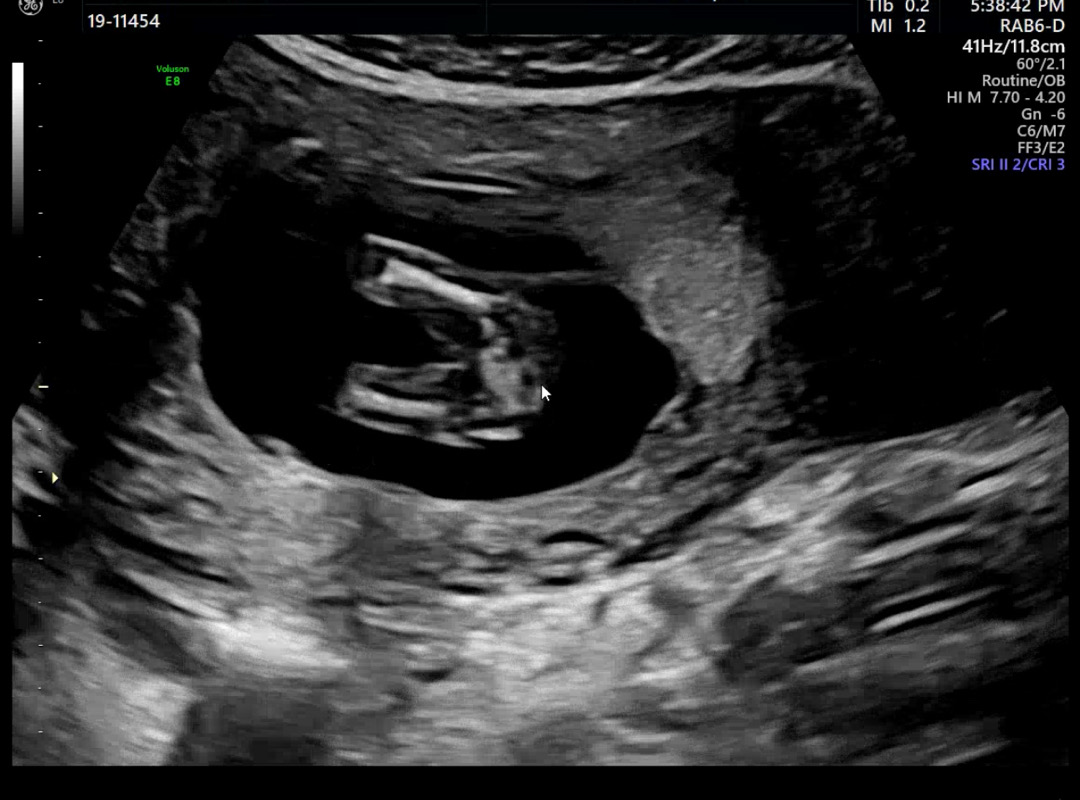

어때보이나요!? 아가 아래쪽화면인거같은데

딸일거같다고 하시네요 어때보이시나요? 14주입니다